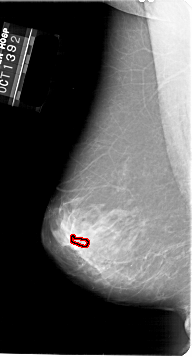

A_1647_1.LEFT_CC

LEFT_CC LINES 6691 PIXELS_PER_LINE 3586 BITS_PER_PIXEL 12 RESOLUTION 43.5 OVERLAY

FILE: A_1647_1.LEFT_CC.OVERLAY

TOTAL_ABNORMALITIES 1

ABNORMALITY 1

LESION_TYPE CALCIFICATION TYPE PLEOMORPHIC DISTRIBUTION CLUSTERED

ASSESSMENT 4

SUBTLETY 1

PATHOLOGY BENIGN

TOTAL_OUTLINES 1

BOUNDARY